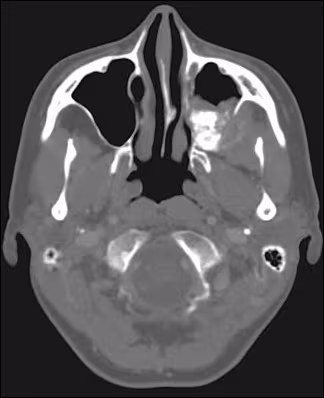

Advanced radiographic imaging using CT scans showed a mass of the left posterior maxilla extending into the maxillary sinus. Considerable expansion of the buccal and moderate expansion of the palatal cortical plate was evident. As noted in the coronal (Figure 4) as well as axial views (Figure 5), the lateral nasal wall was involved but expansion into the nasal cavity was not seen. The internal structure showed patchy calcified areas of varying density and irregular distribution.

Figure 5. CT scan, axial section showing involvement of the lateral nasal wall with minimal expansion into the nasal cavity, although the posterior aspect of the maxillary sinus is filled with the lesional tissue.